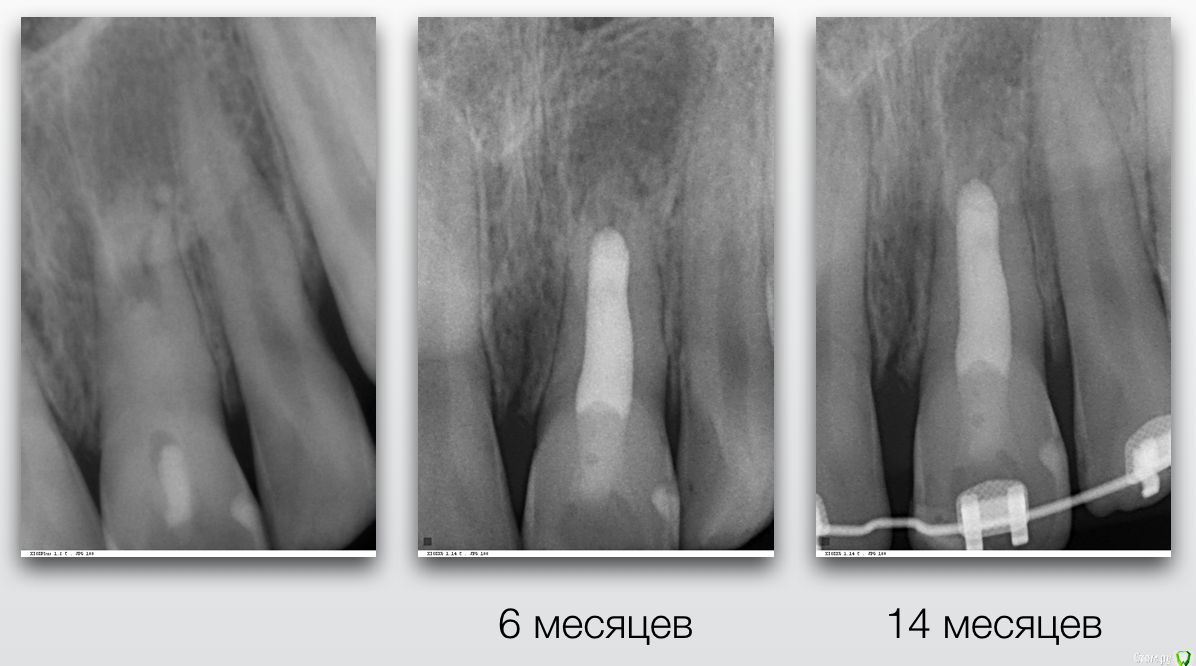

Гарриевич Опубликовано 5 февраля, 2019 Поделиться Опубликовано 5 февраля, 2019 Хочу рассказать одну маленькую историю об одной маленькой девочке, которая произошла не так давно, чтобы ее забыть, но и достаточно давно, чтобы убедиться в её хорошем конце.Утро у нас в клинике всегда начинается с пятиминутки, это время когда мы обсуждаем записанных на день пациентов и планируем лечение... то есть так должно быть, а по правде мы тратим эти 15 минут на обсуждение почему я опоздал, почему снова небритый и где вкуснее готовят кофе)Вообще душевный коллектив это здорово.Так вот на одной из пятиминуток главврач показал мне КТ 11-летней девочки с «кистой» верхнего центрального резца. До нас родители обращались в один большой московский Стоматологический ВУЗ и там и рекомендовали зуб удалить (киста же!), брекеты поставить, а после снятия брекетов и до 21 года ходить со съёмным протезом... у меня все... как вам план?Но есть стоматологи который читают современные книжки и есть пациенты которые читают, в правильных дозах, интернеты, и когда родители пришли к нам и услышали, что зуб не только не надо удалять, но ещё и можно вылечить, то обрадовались и остались лечиться. Всем пациентам довершим мне лечение зубов с «кистами»: спасибо! Прикладываю все усилия, чтобы каждый день это доверие оправдывать. Хорошего дня, Гарриевич. P.S. Разница между снимками 1,5 года 13 Ссылка на комментарий

Гарриевич Опубликовано 6 февраля, 2019 Автор Поделиться Опубликовано 6 февраля, 2019 Спасибо за кейс доктор , всегда приятно смотреть на борьбу со злом которая заканчивается победой "наших".. Расскажите немного о том какой природы была киста(диагноз так понимаю не гистологический) , и какими материалами работали в канале, заранее благодарю . спасибо)кистой я это называю исключительно в целях упрощения понимания пациентами. Конечно это банальный апикальный периодонтит с внушительных размеров резорбциейв канале мта и гутта (горячая) с эпоксидкой Ссылка на комментарий